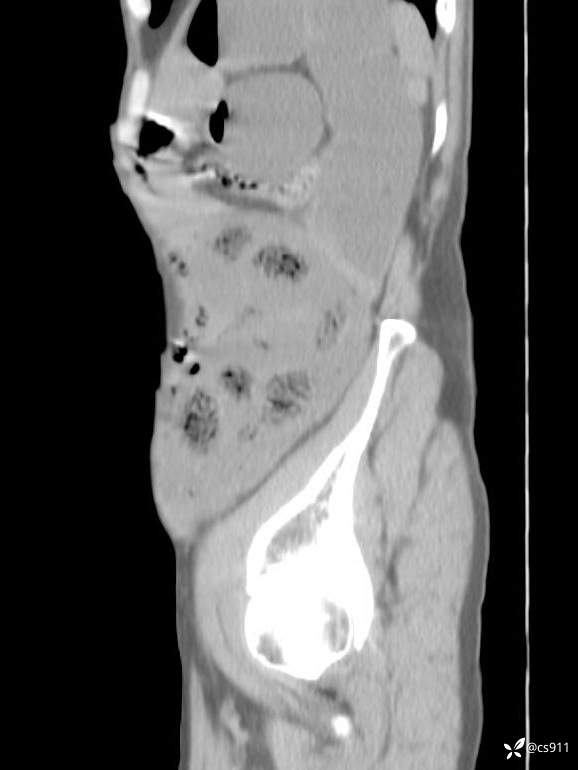

急腹症之急诊CT,原因?答案公布

男,77岁,腹痛、腹胀伴恶心呕吐1天。呕吐胃内容物,非喷射性呕吐,有咖啡色样胃内容物,诉有胃穿孔病史。查体:全腹平,下腹部压痛,全腹无反跳痛,叩诊呈浊音,移动性浊音阴性,肠鸣音减弱,1-2次/分。肛检:直肠未扪及明显肿物,可触及大量粪块。

T 36.6℃ P 80次/分 R 26次/分 BP 100/60mmHg

白细胞(WBC) H 14.55 10e9/L 4-10

红细胞(RBC) 4.58 10e12/L 4.3-5.8

中性粒细胞百分率(NEUT%) H 85.7 % 40-75

血淀粉酶(AMY) HH 1859 U/L 35-135

癌胚抗原(CEA) H 27.44 ng/ml 0-5

呕吐物 潜血试验 * 阳性 阴性

患者轮椅入室检查神志清楚, 能配合摆位和呼吸